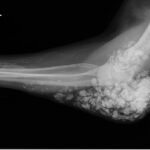

Calcinosis cutis is a condition in which calcium-phosphate salt deposits are formed in cutaneous and subcutaneous tissue. A subtype, metastatic calcinosis cutis, can occur in patients with disorders that cause hypercalcemia or hyperphosphatemia such as end stage renal disease. We present a case of a 67-year-old man with end-stage renal disease (ESRD) on dialysis who presented to the emergency department with a draining left elbow wound. On exam, he had irregular, firm nodules palpable in the subcutaneous tissue of both large and small joints. The presence of calcinosis cutis on imaging and lack of other findings suggesting infection led to outpatient wound care treatment. Recognizing the appearance of calcinosis cutis on imaging and conditions that present with calcinosis cutis is important for the emergency physician.